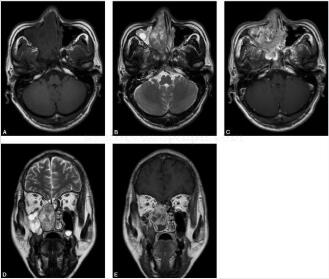

(右鼻腔)多形性腺瘤伴腺样囊性癌区域(图3)

镜下可见瘤细胞梭形及多边形、大小较一致,胞浆界线不清,片状排列,间质黏液变性,部分区域可见瘤细胞呈腺样、筛网状排列,偶见核分裂。诊断为(右鼻腔)多形性腺瘤伴腺样囊性癌区域

光镜下,瘤体组织结构与涎腺多形性腺瘤的结构相似,但鼻腔多形性腺瘤的瘤细胞成分较丰富,细胞小,呈片状、带状排列和形成小腺泡结构,黏液结构多见;且上皮成分在肿瘤组织结构中占主导,甚至可见瘤体完全由上皮成分组成。肿瘤由导管上皮细胞,肌上皮细胞,黏液、黏液样或软骨成分组成:导管上皮细胞多呈立方或矮柱状构成导管样结构,腺管外为梭形或星形的肌上皮,管腔内含有上皮性黏液。肌上皮细胞呈浆细胞样、梭形、透明呈片状或弥漫散在。纤维性间质可呈灶性分布,为黏液、黏液样或软骨样改变。黏液样组织的细胞呈星形和梭形,胞浆突彼此相连成网状;软骨样组织似透明软骨,软骨细胞大小不一,胞浆呈空泡状,有的细胞位于软骨样陷窝中,周围基质嗜酸性。偶可见角化的鳞状细胞灶,也可见圆柱瘤样结构灶,无或罕见核分裂。可见钙化或骨化灶。上皮成分多且有核分裂象者易恶变;而黏液成分多者属良性。